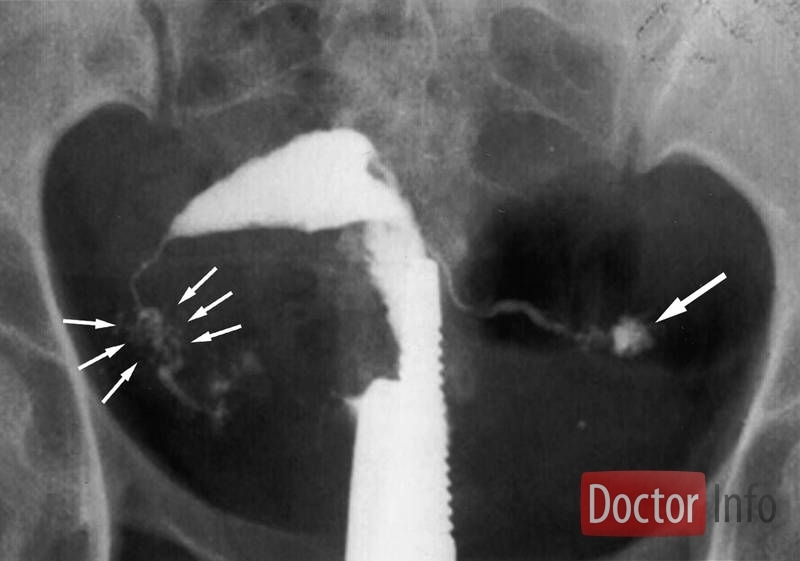

Это метастазирование (распространение) инфекционного процесса из первичного очага (лёгкие, почки, кости чаще всего) в область женских половых органов. Распространение инфекции происходит по кровеносным сосудам с наиболее частым поражением маточных труб, извилистое и складчатое строение которых способствует оседанию и размножению туберкулёзной палочки.